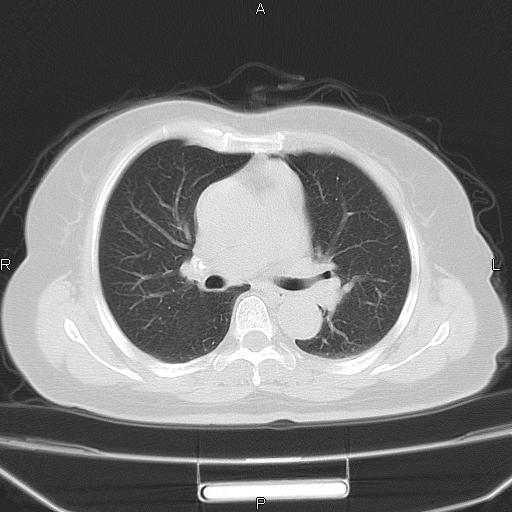

胸腺瘤

女、63Y 双眼睑下垂,早轻晚重。 胸腺瘤???

结果胸腺瘤